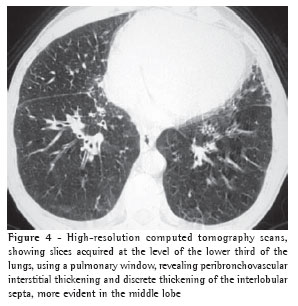

Pleural effusion was the third most common tomographic finding overall and was the most common nonparenchymal finding, being found in 13 patients (87%), predominantly in the bilateral form (n = 11) (Figures 1-3).

Among the eleven patients with bilateral pleural effusion, nine presented asymmetric pleural effusion, predominantly on the right side. Two cases of exclusively right-sided pleural effusion were identified.

Vascular diameter was increased in seven cases (44%) (Figure 3).